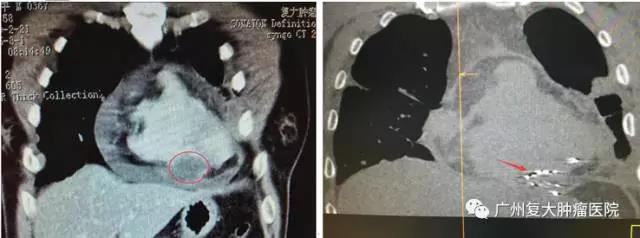

左图:治疗前,CT扫描图像显示肿瘤约4.9×3.8×3.4 cm

右图:治疗后CT复查肿瘤已消融